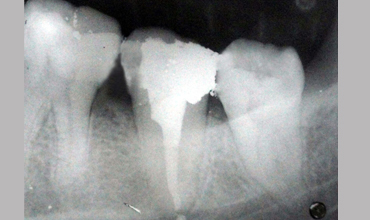

Management Of Single Root

Management Of Single Root With Single Canal In Mandibular Second Molar